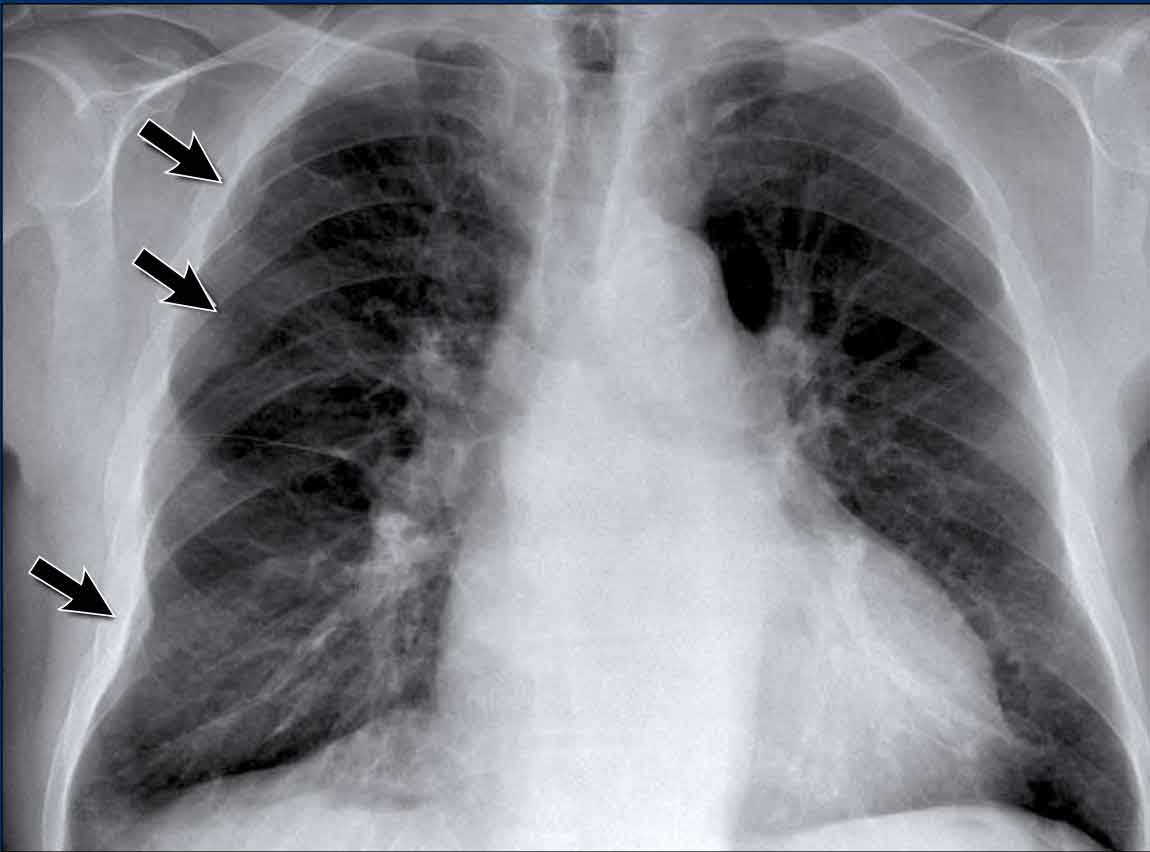

Hilar enlargement - case 1

In this case there is an enlarged hilar shadow on both sides. This could be the result of enlarged vessels or enlarged lymph nodes. A very helpful finding in this case is the mass on the right of the trachea.

This is known as the 1-2-3 sign in sarcoidosis, i.e. enlargement of left hilum, right hilum and paratracheal.

Here some more examples of sarcoidosis.

Click image to enlarge.

- Lymphadenopathy and groundglass appearance of the lungs

- Lymphadenopathy, 1-2-3 sign

- Bulky lymphadenopathy

- 1-2-3 sign

- Nodular lung pattern, no lymphadenopathy

- Hilar and paratracheal lymphadenopathy